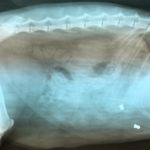

Ktoś strzela z wiatrówki do zwierząt

Na osiedlu Ustronie nieznana osoba strzela z wiatrówki do zwierząt. Ranny został co najmniej jeden kot, który trafił do weterynarza.

Na portalu społecznościowym na stronie...